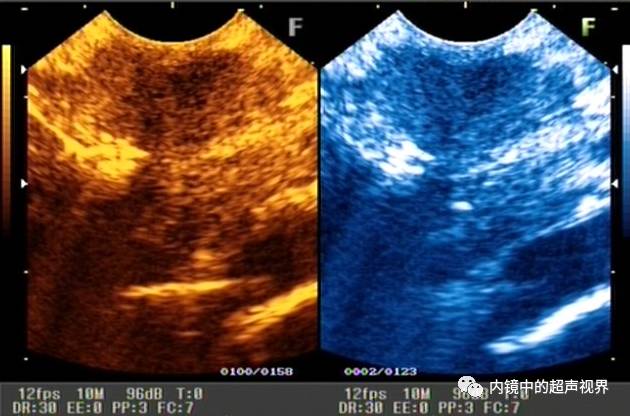

再来一张间质瘤的图片,也是DR30和80的对比。

有没人觉得,这个间质瘤的图片跟前面两个病灶不太一样,似乎感觉高DR模式看起来更舒服,那是因为,间质瘤为低回声,它周围的软组织为高回声,本身就能形成良好的对比,无需降低DR,而高DR模式更显细腻。

再说伪彩,它把黑白图像处理成黑橙、黑绿、黑蓝、黑粉等图像,一定程度上改变了图像的视感,类似于FICE、iSCAN等后处理光学染色功能,萝卜白菜各有所爱,喜欢哪个直接拿走。

间质瘤